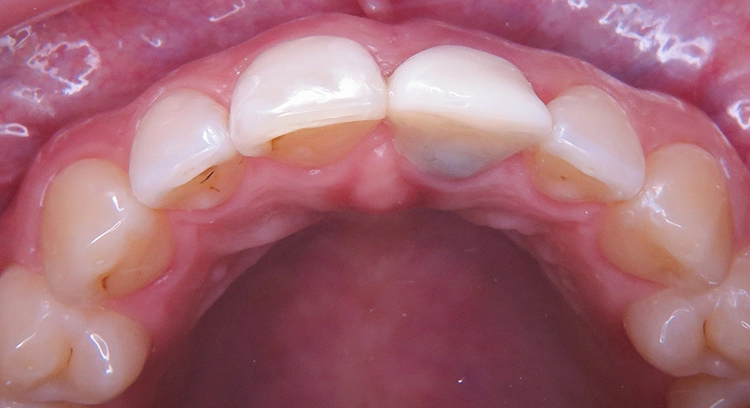

Die junge Patientin konsultierte die Zahnarztpraxis mit Beschwerden am Zahn 21. Der endodontisch vorbehandelte Zahn (multiple Wurzelspitzenresektionen) war mit einer Krone prothetisch versorgt (Abb. 1). Die Krone wirkte im Mund etwas dunkel und hatte einen grauen Schimmer. Da der Zahn zudem immer wieder Beschwerden bereitete, äußerte die Patientin den Wunsch nach einer Neuversorgung. Ansonsten war sie vollbezahnt und funktionell ohne pathologischen Befund. Parodontal zeigte sich eine kleine Rezession im Unterkiefer-Frontzahnbereich.

Zu den schwierigen Anforderungen im Frontzahnbereich gesellten sich hohe ästhetische Ansprüche. Die klinische sowie radiologische Diagnostik (Abb. 2) ergaben, dass der Versuch des Erhalts von Zahn 21 keine sichere Perspektive bot. Die Entscheidung fiel für die Extraktion des Zahnes. Um das Hart- und Weichgewebe bestmöglich vor der physiologischen Remodellierung nach der Extraktion zu bewahren, wurde eine Sofortimplantation geplant.